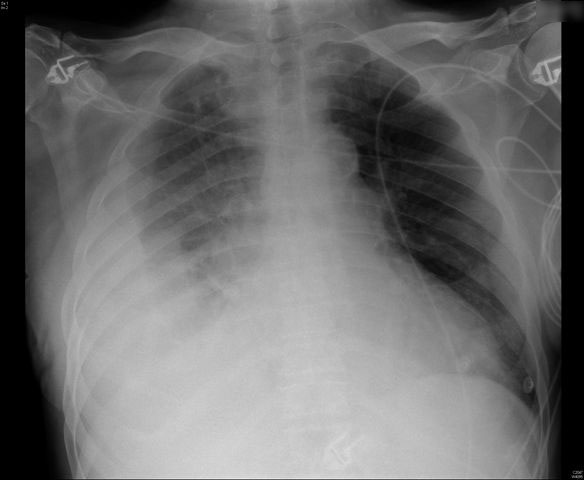

MO Distres respiratorio del adulto por trauma.